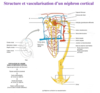

Quelles sont les 3 zones du rein?

- externe (cortex rénal)

- intermédiaire (médullaire rénal ou médulla)

- interne (bassinet)

Que comprend la zone intermédiaire du rein et sa fonction?

- comprend tout les pyramide rénal (trait)

- chargé de retenir l’urine par la terminaire des pyramide (les papille rénal)

Que comprend la zone interne du rein et sa fonction?

interne (bassinet) retient l’urine avant de se déverser dans uretere, calice mineur sont à la terminaison des papile rénal et tous les calice mineur se réunisse pour former le calice majeur